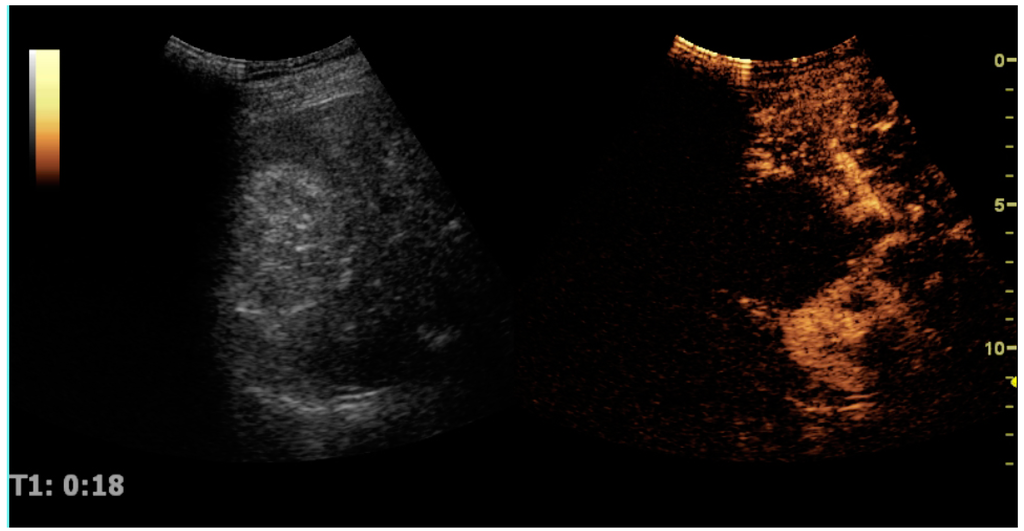

CEUS can evaluate microvasculature, which color Doppler US is unable to detect. In renal US examination, CEUS can be used to differentiate tumor and pseudotumor, such as prominent columns of Bertin. Pseudotumors enhance as adjacent renal tissue. The use of CEUS is recommended in special cases to distinguish between cystic and hypovascularized solid lesions, to characterize complex cysts, abscesses, traumatic lesions and ischemic lesions [35,36]. Solid malignant tumors in the kidney do not exhibit specific enhancement patterns like some liver lesions, and no valid enhancement criteria between benign and malignant renal lesions have been proposed [37,38]. However, CEUS is used in some patients after ablation of renal cell carcinoma to evaluate contrast uptake in the treated area (Figure 30).

Figure 30. Renal cell carcinoma successfully treated with thermal ablation, as no contrast enhancement is seen.